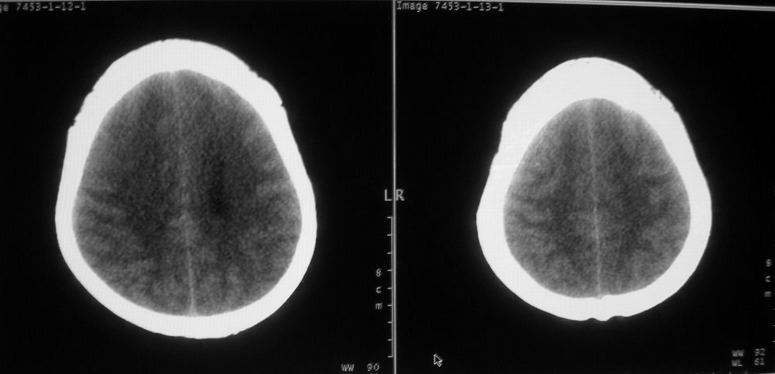

标题: CT18148:女,44岁,头痛数月。 [打印本页]

女,44岁,头痛数月。

右侧额叶占位性病变,考虑脑肿瘤;建议行进一步检查。

右侧额叶占位性病变,考虑脑膜瘤可能性大;建议行进一步检查。

考虑为额叶占位;肿瘤可能?建议行进一步检查。